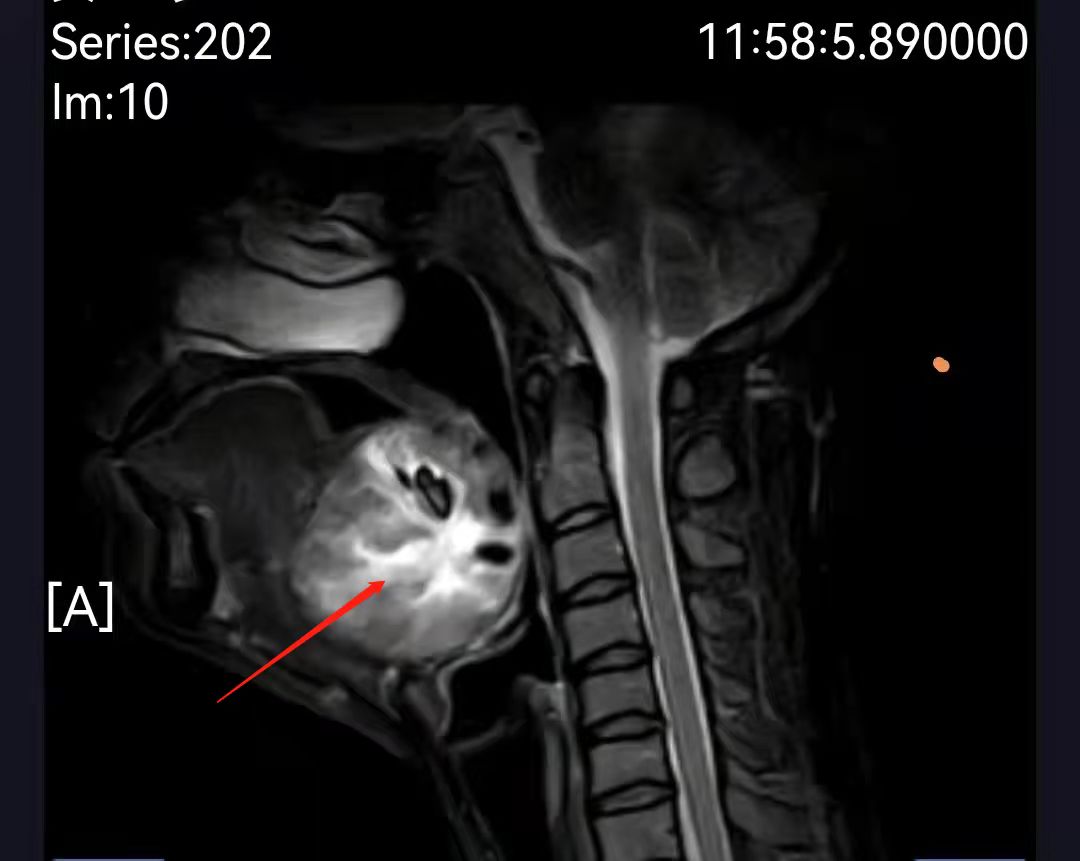

26岁的孕妇谭女士,妊娠28周,年少时曾做过一次甲舌囊肿手术,两年前在一家大医院诊断出“异位甲状腺并血管畸形”,因手术风险大一直保守治疗。患者怀孕后出现甲状腺功能低下合并反复口咽部活动性出血,随孕期增长,出血频率越来越多出血量越来越大,每次达200-300ml,多方就医均因保胎风险太大未行手术。近期舌根部肿瘤迅速长大,患者出现说话含糊、呼吸困难症状,最近一次出血量达500ml,命悬一线,患者被紧急转往湘雅三医院耳鼻喉科急诊入院。

患者入院后口咽部仍反复多次出现活动性出血,每次量约200ml,经检查,患者不仅患有“异位甲状腺合并滤泡腺瘤”,且伴有“颈部血管畸形”,畸形血管的脆性极大,随时都有大出血和窒息的风险,孕妇和胎儿都面临极大的生死考验。谭国林教授团队立即组织麻醉科、产科、内分泌、营养科、临床药学等多学科会诊,充分评估手术风险,制定个体化的诊疗方案,入院后即积极完善术前准备,予以输血和营养改善,提高手术耐受性;在产科指导下使用糖皮质激素,促进胎儿肺泡的成熟,以应对万一早产的风险;临床药学和麻醉科拟订最佳麻醉方案,减少麻醉用药对孕妇和胎儿带来的影响;营养科指导留置胃管,术后及早予以肠内营养,保证营养供给。